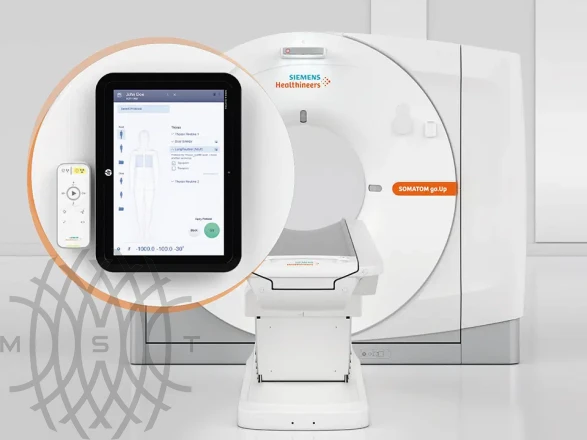

Siemens SOMATOM go.Up компьютерный томограф

SOMATOM go.Up - компьютерный томограф для проведения рутинных и целевых осмотров, лучевой терапии и ангиографии. Система отличается инновационным дизайном рабочего места и полностью обновлённой концепцией сервиса, которая способствует снижению расходов по эксплуатации. Подходит для обследования головного мозга, легких, толстой кишки, сердца, сосудов. Вы можете заказать или купить со склада в наличии компьютерный томограф Siemens SOMATOM go.Up по выгодной цене, от надежного официального дистрибьютора "МСТ", с бесплатной доставкой в любой город по всей России.

Система SOMATOM go.Up основана на новом мобильном рабочем процессе, в ней реализован ряд инновационных решений, которые обеспечивают высочайший уровень гибкости и мобильности в повседневных КТ-исследованиях. Эти решения также помогают повысить уровень комфорта для пациента и в перспективе обеспечат высокий уровень их удовлетворенности.

- Лёгкий планшет с высоким разрешением экрана дает полную свободу в организации работы

- Благодаря технологии Scan&GO для выполнения всего сканирования требуется лишь несколько шагов

- Вы можете проверить информацию о пациенте, как только пригласите его на исследование, и сразу же планировать сканирование на планшете, не отходя от пациента

- Вы все время находитесь рядом с пациентом, контролируя все процессы

Благодаря КТ-системе SOMATOM go.Up медперсонал может проводить большую часть времени с пациентом – это повышает эффективность подготовки, точность и контроль инструкций, это более комфортно для пациента и позволяет предотвратить двигательные артефакты.

- Простой в использовании пульт дистанционного управления с Bluetooth-каналом связи повышает мобильность рабочих процессов

- Пульт упрощает сканирование и повышает эффективность рабочего процесса

- Приложение для планшетных компьютеров, предназначенное для дистанционного управления сканированием

- Возможность управления томографом из процедурной или другого помещения

- Ускорение подготовки и позиционирования пациента

Guide&GO – инновационное решение на основе планшета, которое предназначено для проведения интервенционных процедур под контролем КТ. Оператор может выполнять процедуру с помощью планшета и пульта дистанционного управления, а для работы с изображениями использовать удобные функции сенсорного экрана, которые знакомы любому пользователю смартфона.